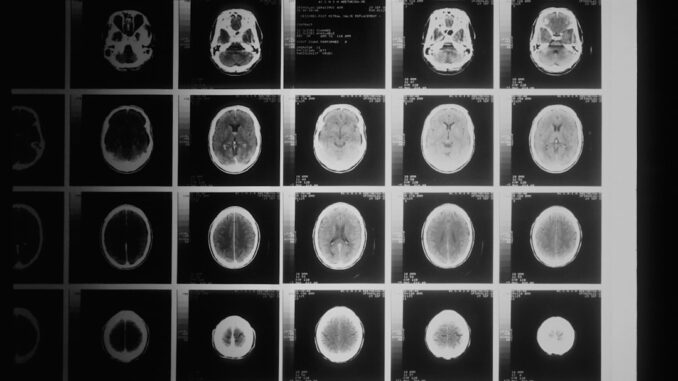

- Convolutional Neural Networks (CNNs): CNNs have emerged as the undisputed champions in the realm of medical image analysis. Inspired by the human visual cortex, CNNs are particularly adept at processing grid-like data, such as images. Their architecture typically comprises convolutional layers (which apply filters to detect features like edges, textures, and patterns), pooling layers (to reduce dimensionality and retain essential information), and fully connected layers (for classification). In diagnostics, CNNs have demonstrated exceptional performance in interpreting medical images across modalities like X-rays, CT scans, MRI, and ultrasound. For instance, sophisticated CNN architectures can accurately detect subtle intracranial hemorrhages, identify spinal fractures that might be missed by the human eye, and pinpoint pulmonary embolisms with remarkable speed and precision, significantly enhancing diagnostic accuracy and efficiency (en.wikipedia.org). Advanced CNNs are also employed for tasks such as tumor segmentation, organ delineation, and the quantification of disease burden, providing objective metrics that aid radiologists and clinicians.

- Detection and Characterization: AI excels at identifying subtle anomalies that might escape human detection due to their size, location, or the sheer volume of images. For instance, in oncology, AI systems can detect lung nodules on CT scans, breast microcalcifications on mammograms, and prostate lesions on MRI with high sensitivity, often flagging suspicious areas for human review. Studies have shown AI systems to achieve superior performance in reducing false positives and negatives in mammography screenings compared to human radiologists, thereby minimizing unnecessary biopsies and improving patient experience (time.com). Beyond cancer, AI aids in detecting acute conditions like intracranial hemorrhage on head CTs, pneumothorax on chest X-rays, and acute appendicitis on abdominal CTs.

- Neurological Disorders: AI aids in the early detection of neurodegenerative diseases like Alzheimer’s and Parkinson’s by analyzing subtle changes in brain MRI or PET scans, and in stroke assessment for timely intervention.

- Workflow Optimization: AI tools can prioritize urgent cases by flagging critical findings, reducing radiologists’ workload, and decreasing turnaround times for reports. They also automate measurements (e.g., tumor volume tracking, organ size) and generate quantitative reports, adding objectivity and consistency.

- Image Reconstruction and Enhancement: AI can reconstruct high-quality images from limited raw data, reduce imaging artifacts, and denoise images, potentially leading to lower radiation doses or faster scan times without compromising diagnostic quality.